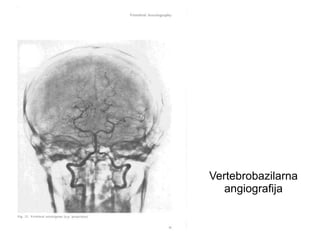

Vertebrobazilarna

angiografija